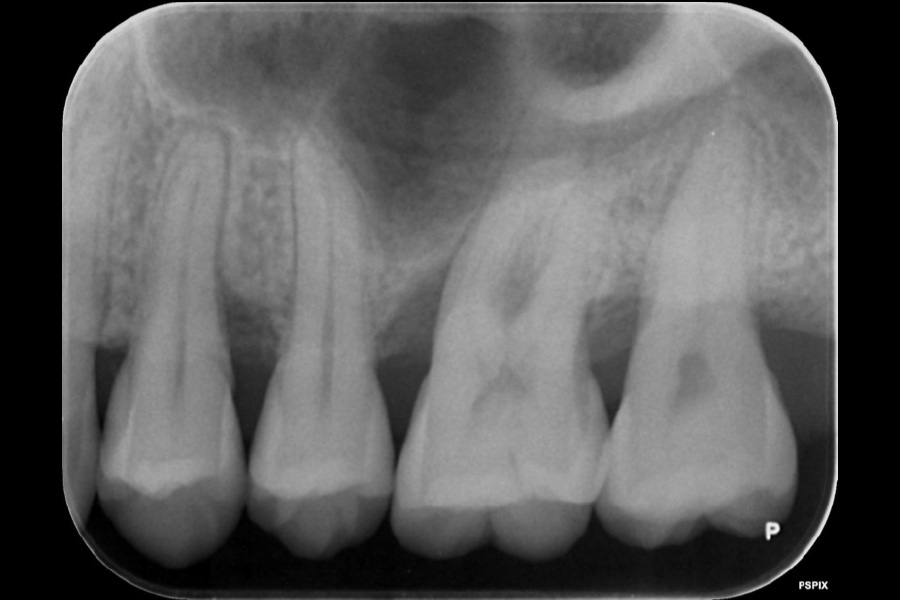

上の前歯の歯ぐきが腫れた

【歯周組織再生療法】

- 主訴

- 上の前歯の歯ぐきが腫れた

- 期間

- 再生療法から再評価まで6か月

- 費用

- ¥220,000(税込)

- 治療内容

- 左上3近心に垂直性骨吸収が認められたためエムドゲインと骨補填材を用いて歯周組織再生療法を行った

- 治療に伴うリスク

- 歯肉退縮、知覚過敏